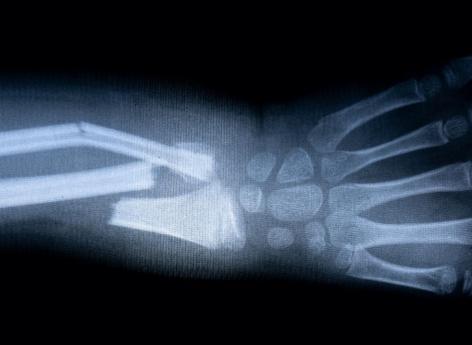

Les nouvelles technologies permettent de capturer de nouvelles images en temps réel de la formation des os et des dents. Une meilleure connaissance du processus qui permet d’envisager une accélération du processus de cicatrisation osseuse. Dans des travaux publiés le 18 novembre dans la revue Science Advances, des chercheurs américains de l’université de l’Illinois à Chicago ont décrypté avec une précision inégalée le processus par lequel les minéraux se combinent au niveau moléculaire pour former des os et d'autres tissus durs.

L’étude a identifié in vitro les voies de minéralisation et de cristallisation de l'hydroxyapatite (HA), un minéral de la famille des phosphates, qui forme la base de nos tissus osseux. À l’aide d’une microscopie électronique à transmission dans une solution de salive artificielle, ils se sont rendus compte que la formation directe et indirecte de cristaux d'hydroxyapatite peut être obtenue en régulant la dissolution du phosphate de calcium. Une découverte qui est un grand pas vers un meilleur traitement des fractures osseuses mais aussi des maladies caractérisées par des déficiences de minéralisation, comme l'ostéoporose.

“En utilisant notre technologie, nous avons pu décrypter ces voies et mieux comprendre comment les particules d'hydroxyapatite se nucléent et se développent sur des modèles de phosphate de calcium, a détaillé le Dr Rez Shahbazian-Yasser. La compréhension de ce processus de cristallisation va nous permettre de développer de nouveaux médicaments pour accélérer la réparation osseuse des fractures ou pour traiter les caries dentaires.”

Ces découvertes permettent de reproduire ou accélérer le processus de biominéralisation pour la cicatrisation ou la régénération osseuse. “Notre étude fournit de nouvelles données claires sur la façon dont les minéraux s'organisent et se transforment en tissus osseux, et cette découverte a de nombreuses implications pour la cicatrisation des os ou des dents”, conclut le chercheur.